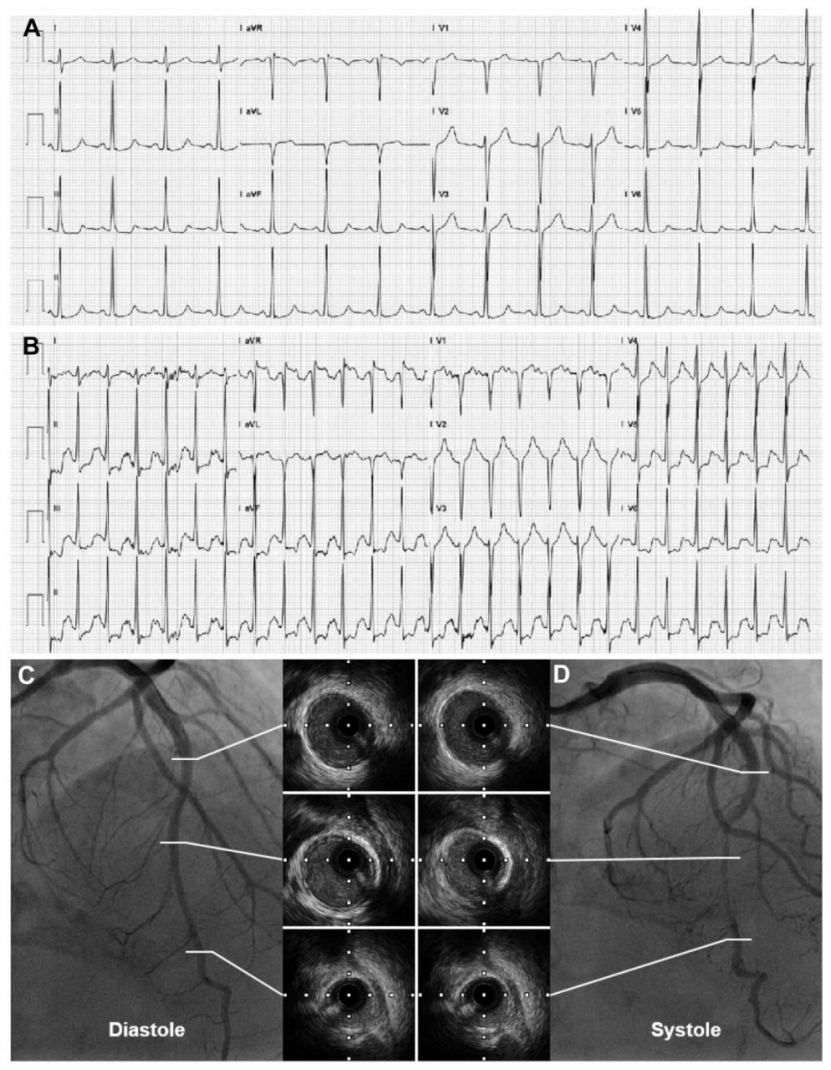

上海中山医院葛均波等提出左前降支心肌桥的葛氏三联征

st-t改变⚠️冠心病心肌缺血?别慌!

心电图st段变化